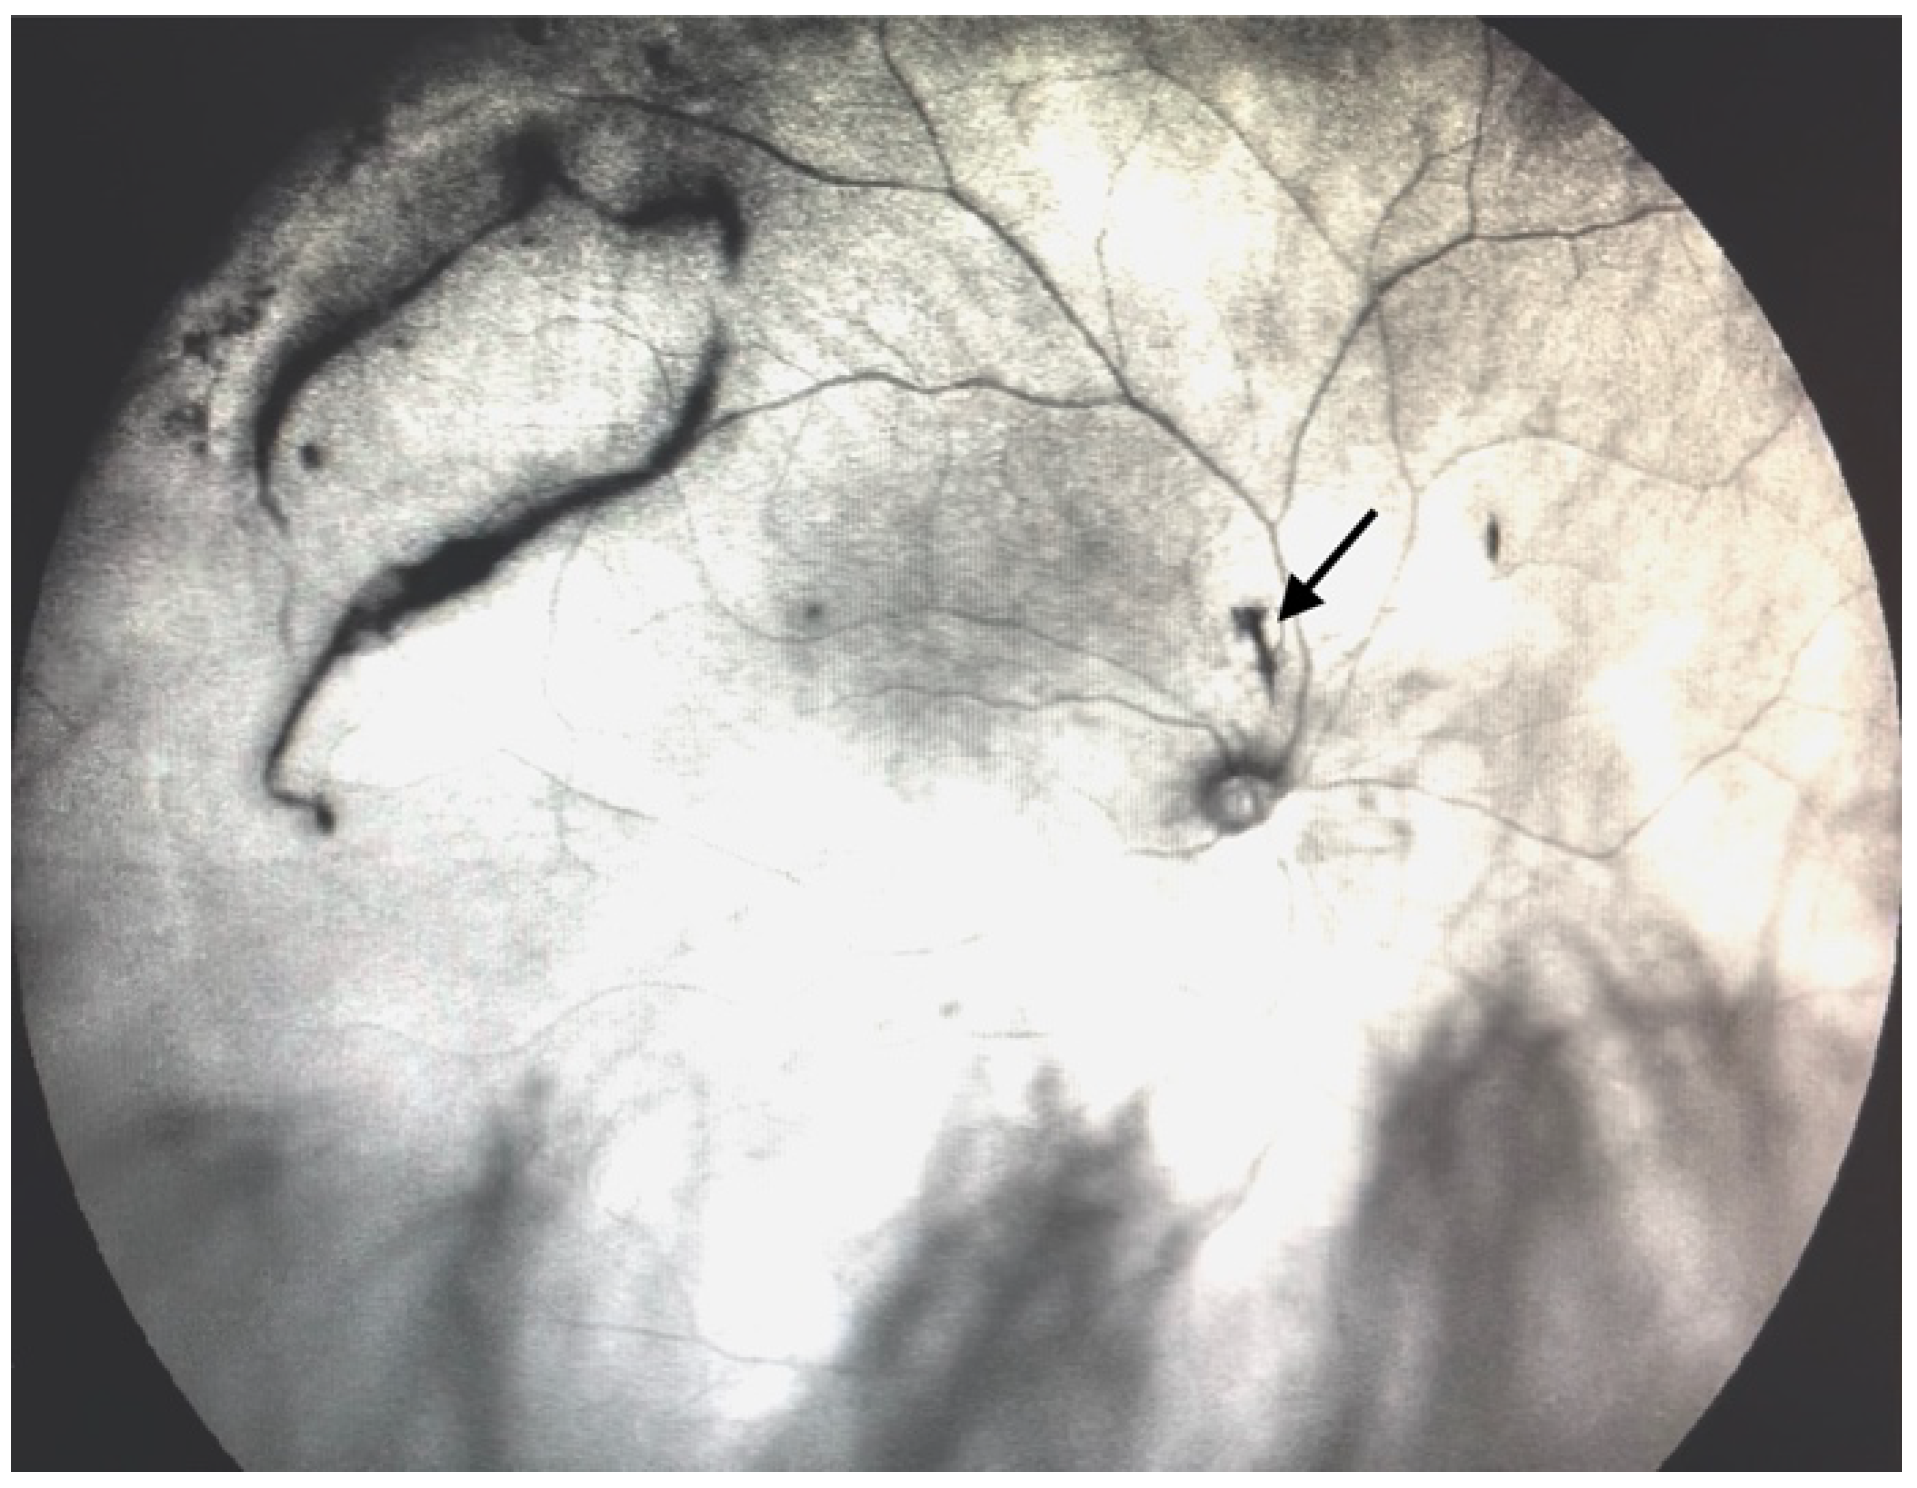

Figure 4.

Ultra-widefield IRcSLO image of an eye with Grade 2 vitreous floaters. Dense shadows are observed outside the macular area, in the superotemporal periphery, overlying an area of lattice degeneration. A Weiss ring is also visible outside the macular area (arrow). See also Video S4.